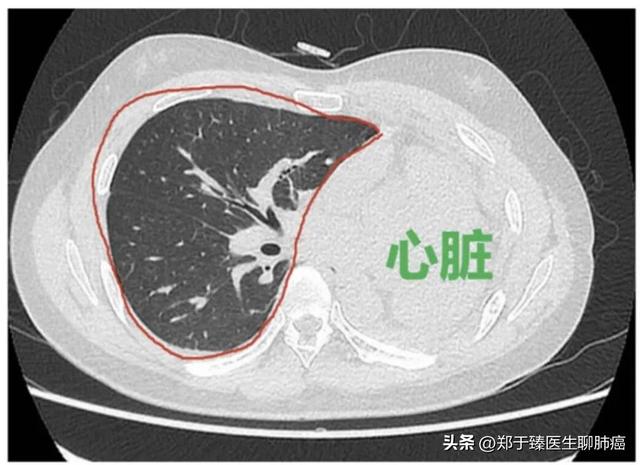

从上面这张图中,我们可以直观地感受到肺手术造成的内伤程度。

同侧的肺会复张,填补空缺的空间;对侧的肺也会复张,推动心脏移位,最终完全填补丢失的肺功能。

例如,左上肺切除后,下面的肺会膨胀,对侧的肺也会膨胀,推动心脏向左移位,填补左上肺切除后的空缺。

这是一个左上肺叶切除术后的患者。手术后,随着恢复时间的延长,左肺和右肺都开始膨胀。

到了术后半年,残存的肺部基本填满了整个胸腔,心脏(红色轮廓部分)也被推动到更靠左的位置,表明肺部已经接近涨满,完成了代偿。